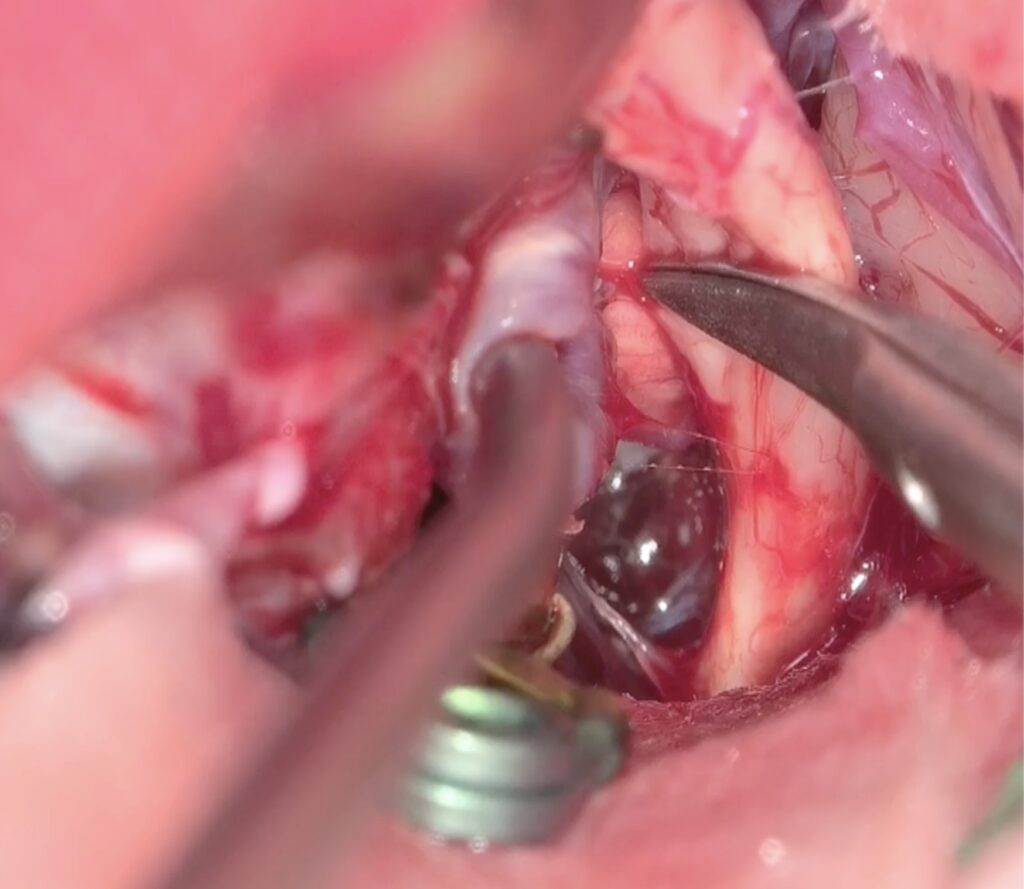

最近のこの場所の動脈瘤クリッピング術が増えています。4mm以上の上向き動脈瘤で術前BTOで虚血耐性のあるものを適応としています。ICG、MEP、VEG、術中血管撮影など術中画像、電気生理学モニタリングをしっかり準備して行っています。本例も視神経下面と癒着しており、剥がすときに破れましたが、問題なくクリップできています。術後の視機能も良好でした。

術後嗄声と2/23より髄液鼻漏れがあり、CTで左篩骨洞に髄液貯留があり5日間の腰椎ドレナージを行い、治癒しました。